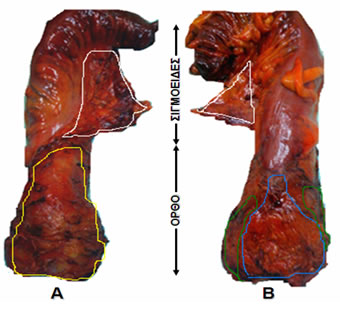

Μακροσκοπικά, διακρίνονται σε έμμισχους και άμισχους (Εικόνα 1).

Εικόνα 1.

Α. Έμμισχος σωληνολαχνωτός αδενωματώδης πολύποδας που αφαιρέθηκε χειρουργικά.

Β. Ευμεγέθης άμισχος λαχνωτός αδενωματώδης πολύποδας ορθού που αφαιρέθηκε χειρουργικά διά του ορθού.

(Από το προσωπικό αρχείο του Γ. Θεοδωρόπουλου)

Εικόνα 2.

Επιμήκως διανοιγμένο παρασκεύασμα πολύ χαμηλής πρόσθιας εκτομής (ολικής αφαίρεσης ορθού) για την αντιμετώπιση ευμεγέθους λαχνωτού αδενώματος (μπλε βέλη), που παρουσίαζε υψηλόβαθμη δυσπλασία χωρίς κακοήθεια. Ο ασθενής εμφανίστηκε με εκκριτικού τύπου διάρροιες, αφυδάτωση και υποκαλιαιμία, που συχνά προκαλούνται από μεγάλα αδενώματα του ορθού. Λόγω του μεγέθους του η τοπική εκτομή του δεν ήταν εφικτή και απαιτήθηκε αφαίρεση του ορθού. Ακολούθησε κολο-πρωκτική αναστόμωση για την αποκατάσταση της συνέχειας του τελικού τμήματος του πεπτικού σωλήνα.

(Από το προσωπικό αρχείο του Γ. Θεοδωρόπουλου)